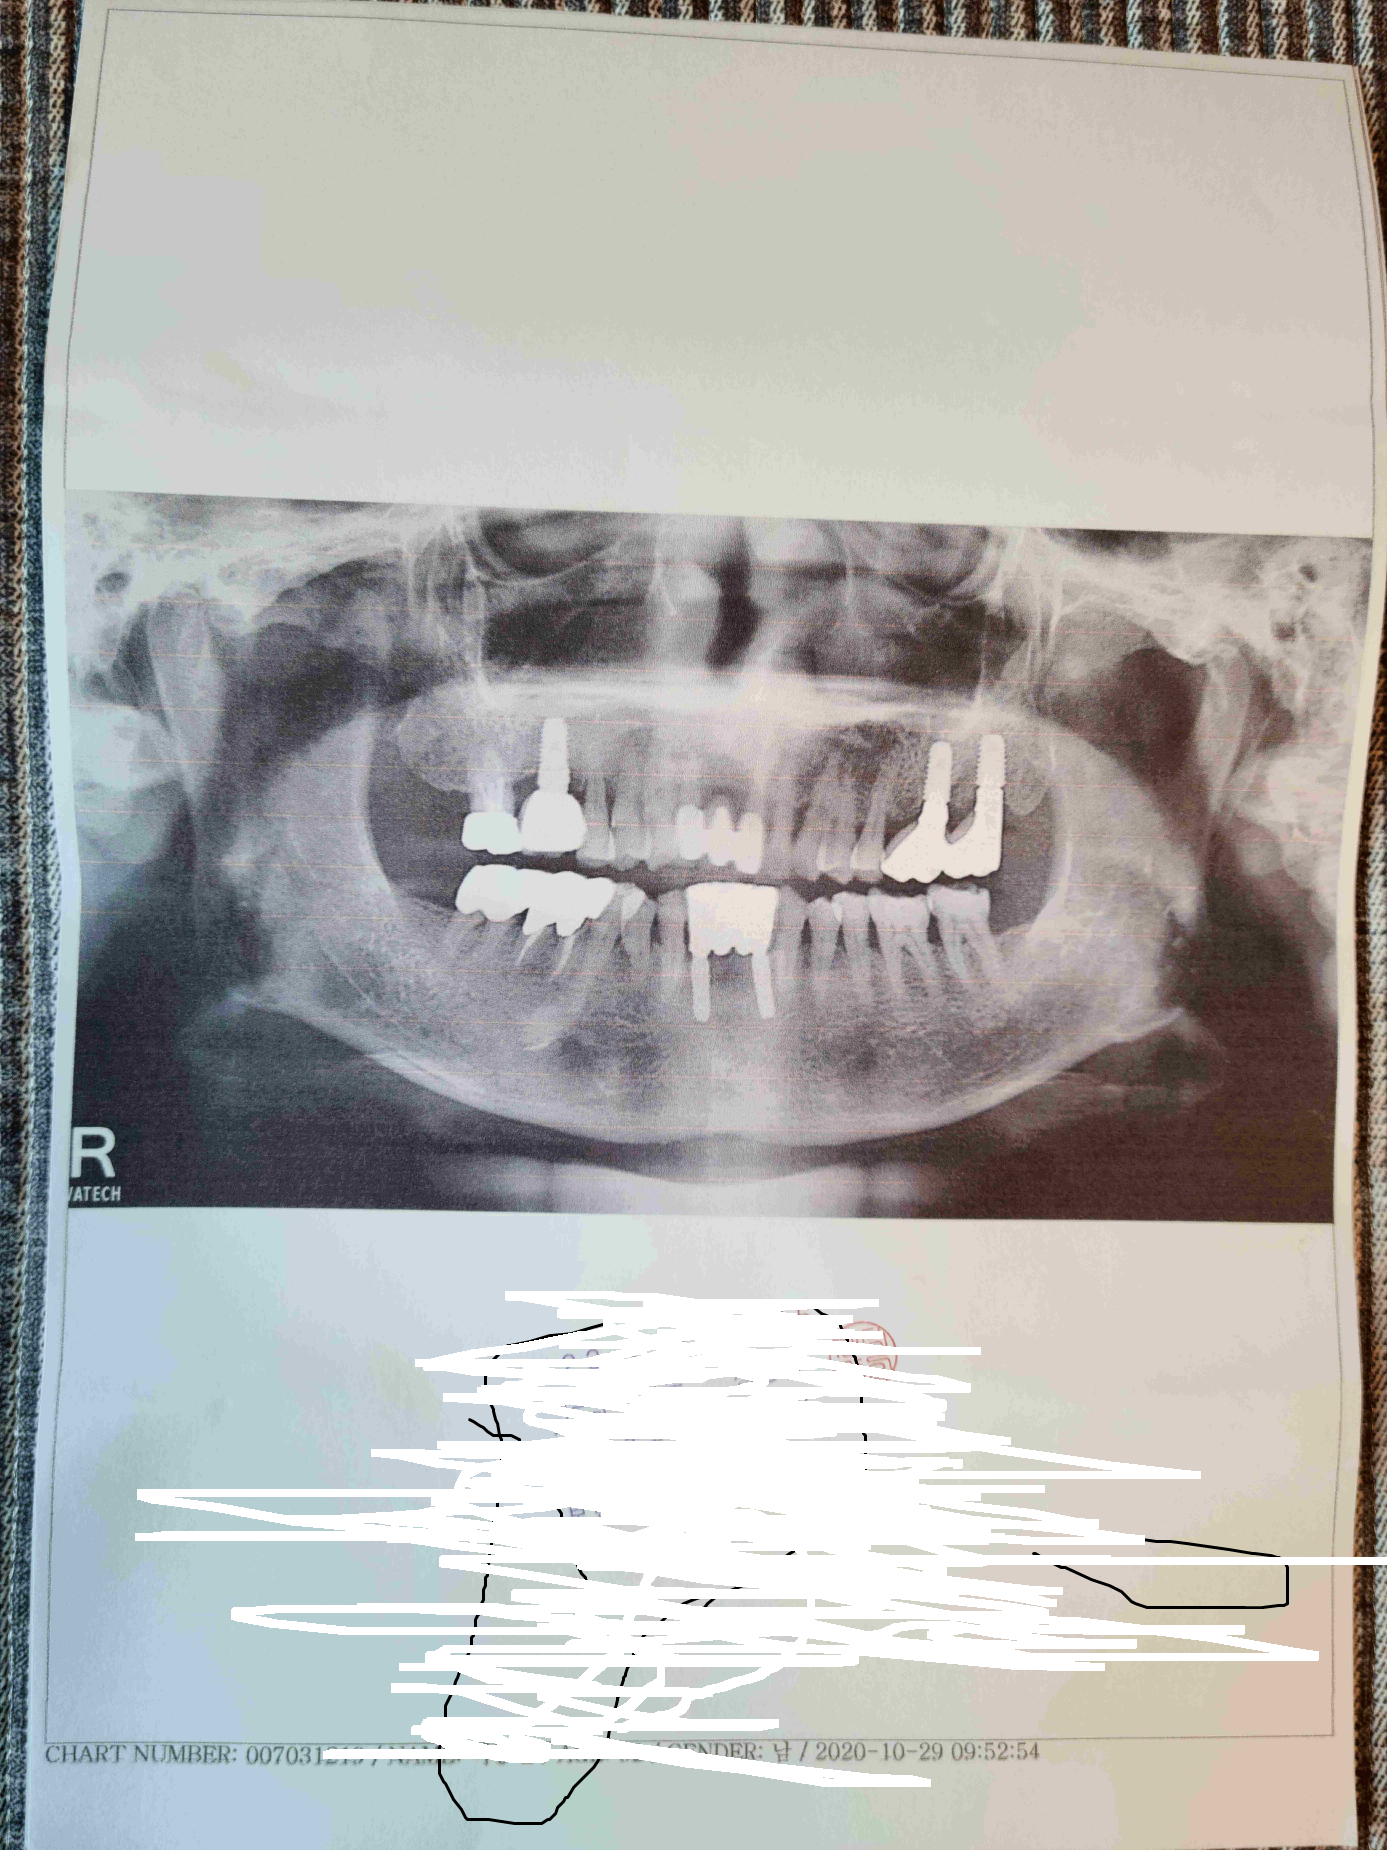

발치를 하고 8개월이 지나 임플란트를 했다.

전반적으로 치아의 상태가 불량하여 상하좌우로 나누어 임플란트 및 레진과 크라운등의 치료를 매주마다 하였고

발치서부터 8개월여가 경과되었다.

병원도 이사 때문에 안중과 금정으로 나누어 치료를 받았으며 거의 삼백가까운 비용이 들었다.

이미 임플란트가 4~5개,크라운등등 반이상이 내것이 아닌것이 들어와있는 상태이다.